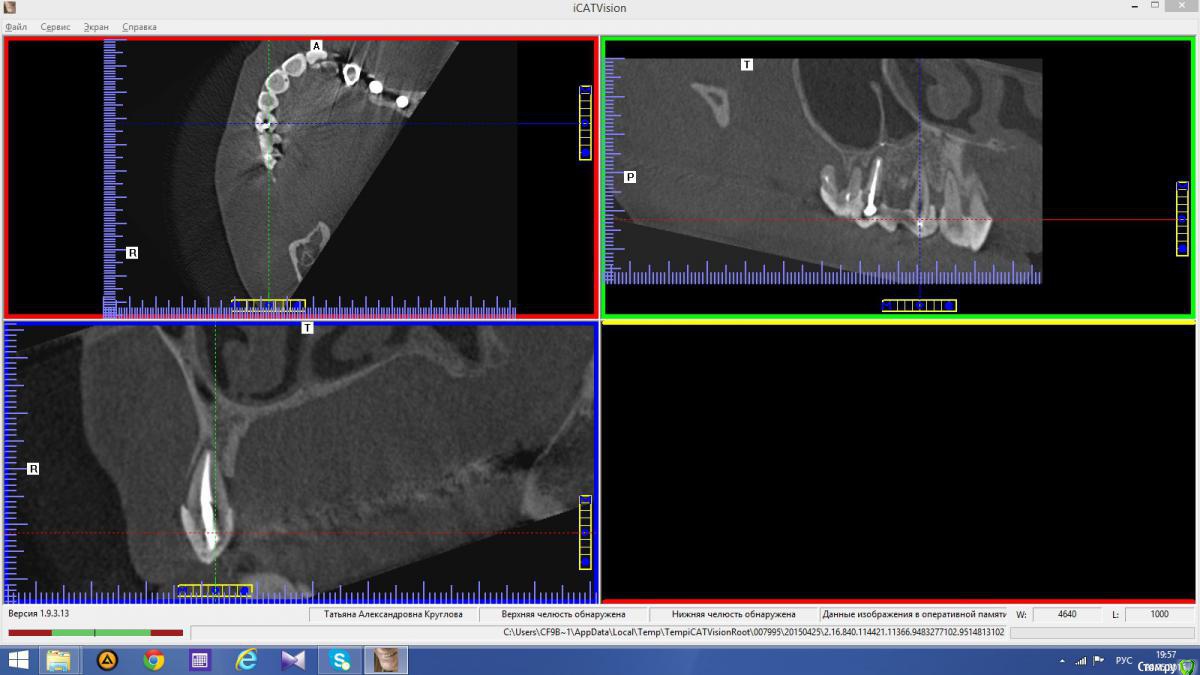

anvladd Опубликовано 24 ноября, 2015 Поделиться Опубликовано 24 ноября, 2015 Снимки не могли бы показать? Ссылка на комментарий

Abuk Опубликовано 24 ноября, 2015 Автор Поделиться Опубликовано 24 ноября, 2015 Снимки не могли бы показать? .все что есть готовое. Ссылка на комментарий

Abuk Опубликовано 24 ноября, 2015 Автор Поделиться Опубликовано 24 ноября, 2015 (изменено) Радикально Вы. Что оставили ей после имплантации-это инд аббатменты? На них мокап одели и нагрузили сразу? У всех был торк хороший? Или это временные абб? Что за систему использовали? В планах консоль назад, правильно я понимаю?Спасибо.увидев такую работу,сам так же подумал бы). Но там подвижность 2-3 ст. ближе к 3. Мосты болтались ,2 ки в хлам. 1 ки только стабильны. Снимал мосты,проводил кюретаж. Решил дернуть.Абатманы временные, тех. сделал на них коронки. Система анкилоз. Работа,на посл. фото, постоянная . Имплы в области 4 и по одному моляру ,консоли. Мок ап был до имплантации . По нему шаблон. Стабильность 15 -20 на 23 , остальное больше 30. Изменено 24 ноября, 2015 пользователем Abuk 1 Ссылка на комментарий